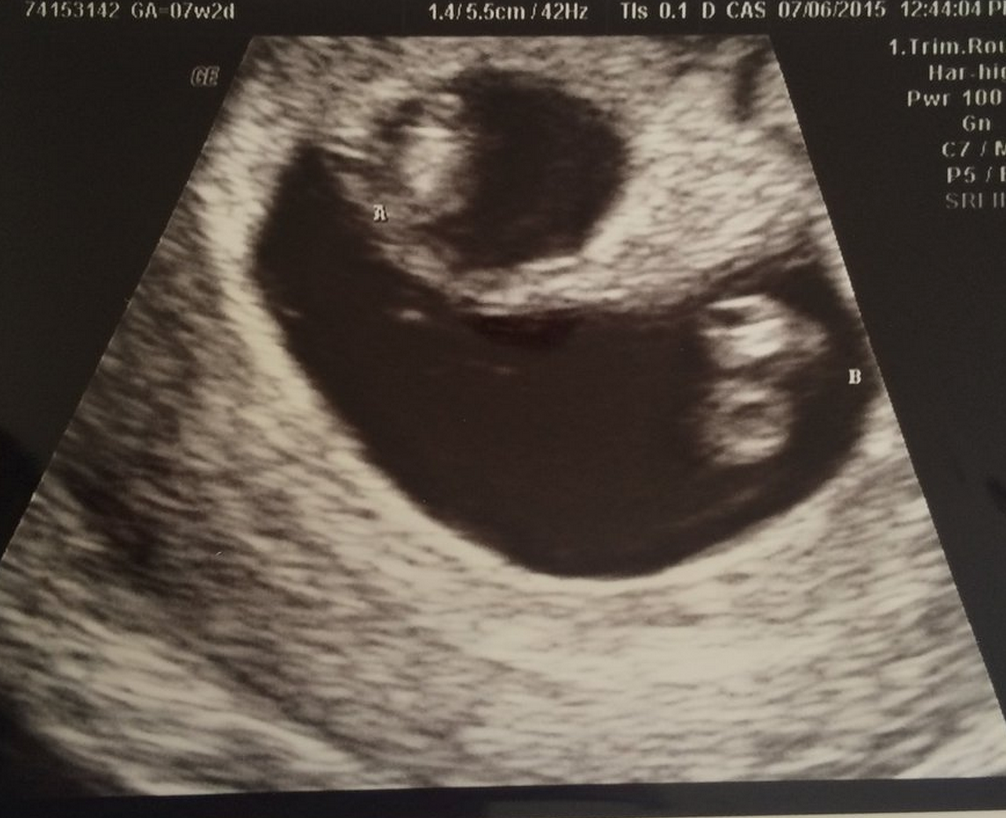

• So glad I get to finally post on this thread! First US today. I was really worries because my progesterone was low, but baby looks good :) heartbeat was 143. Not as far along as we originally thought, but not far behind. Right at 7 weeks. Due 2/23 :)